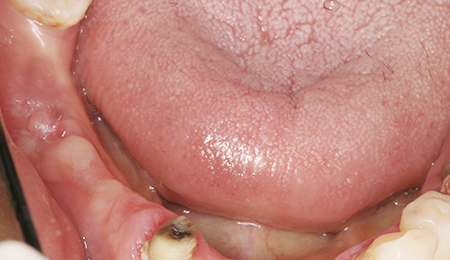

- BEFORE

- AFTER